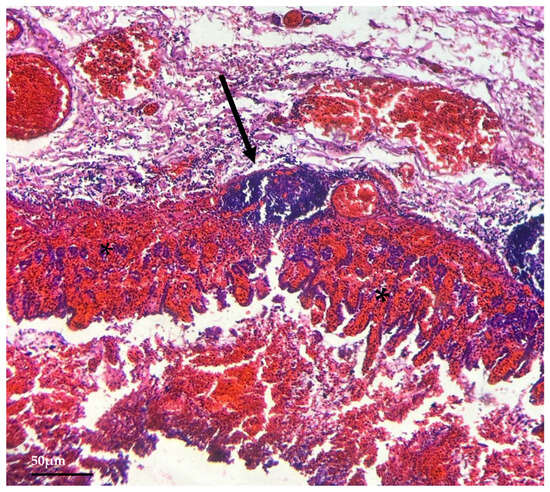

3.3. Histological Findings